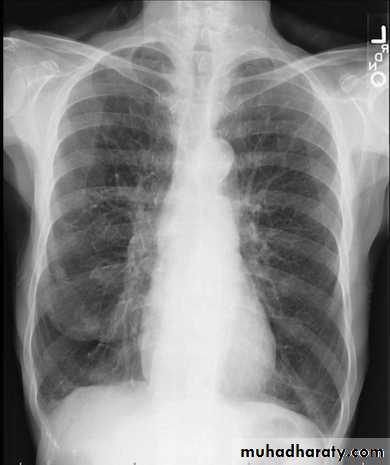

PneumothoraxPneumothorax refers to the presence of gas (air) in the pleural space. When this collection of gas is constantly enlarging with resulting compression of mediastinal structures it can be life-threatening and is known as a tension pneumothorax

A pneumothorax is, when looked for, usually relatively easily appreciated. Typically they demonstrate:

visible visceral pleural edge see as a very thin, sharp white line

no lung markings are seen peripheral to this line

the peripheral space is radiolucent compared to adjacent lung

the lung may completely collapse

the mediastinum should not shift away from the pneumothorax unless a tension pneumothorax is present